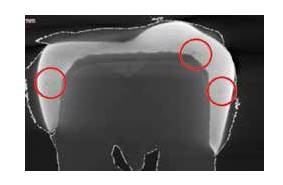

A study by V. Jardel and colleagues fabricated cobalt-chrome metal crowns with SLM, revealing efficient production of up to 16–200 elements simultaneously in 4 - 12 hours. The polished crowns exhibit high metal density but may also exhibit some porosities (Figure 8), requiring post-production polishing to improve adaptation and surface quality. This study highlights the limitations of metal crowns and encourages the use of SLM for the fabrication of metal copings and inlay-cores [24].

Figure 9. X-ray of an SLM-printed crown showing porosities [24].